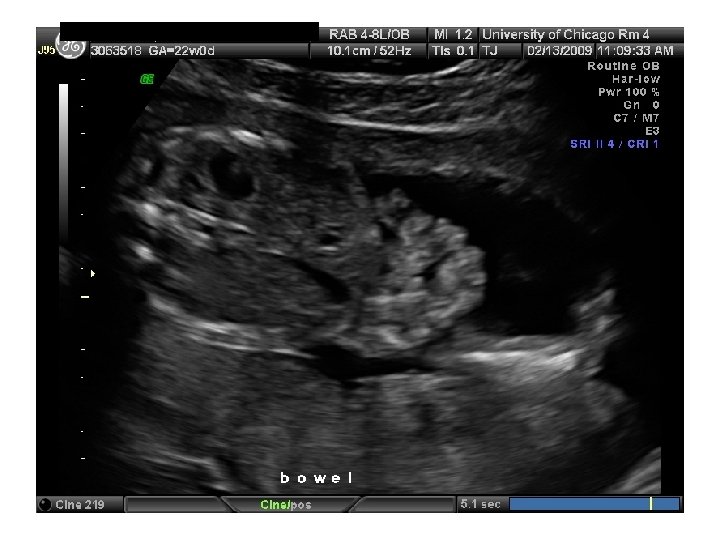

QUIZ What is Your Diagnosis? Case: Patient J. F. 30 years old, at 32 week gestation. Presented with the following pictures.

Answer: a) Trisomy 21 b) Non-immune Hydops c) Paravo virus Infection